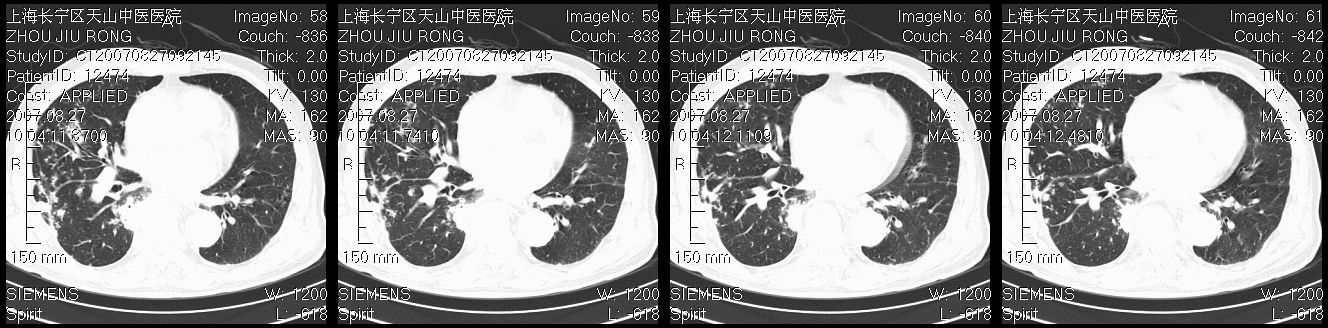

以下是引用zjzjr在2007-8-30 21:47:00的发言:[br]双肺弥漫性结节状、斑片状影,部分形成空洞,病灶以双肺上叶为著(符合结核发病部位),纵隔内见肿大淋巴结影。支持双肺继发性结核伴右上肺空洞形成。

以下是引用zjzjr在2007-8-30 21:47:00的发言:[br]双肺弥漫性结节状、斑片状影,部分形成空洞,病灶以双肺上叶为著(符合结核发病部位),纵隔内见肿大淋巴结影。支持双肺继发性结核伴右上肺空洞形成。

以下是引用gaoshengjiang在2007-8-31 10:24:00的发言:[br]双肺弥漫性斑片状影及多发空洞影,其间夹杂多量条索状影,胸膜肥厚、粘连并有结节状改变,纵隔多枚淋巴结肿大,考虑1双肺继发型肺结核合并感染?2韦格氏肉芽肿?[br] 支持!

以下是引用zjzjr在2007-8-30 21:47:00的发言:[br]双肺弥漫性结节状、斑片状影,部分形成空洞,病灶以双肺上叶为著(符合结核发病部位),纵隔内见肿大淋巴结影。支持双肺继发性结核伴右上肺空洞形成。

以下是引用zjzjr在2007-8-30 21:47:00的发言:[br]双肺弥漫性结节状、斑片状影,部分形成空洞,病灶以双肺上叶为著(符合结核发病部位),纵隔内见肿大淋巴结影。支持双肺继发性结核伴右上肺空洞形成。

以下是引用zjzjr在2007-8-30 21:47:00的发言:[br]双肺弥漫性结节状、斑片状影,部分形成空洞,病灶以双肺上叶为著(符合结核发病部位),纵隔内见肿大淋巴结影。支持双肺继发性结核伴右上肺空洞形成。